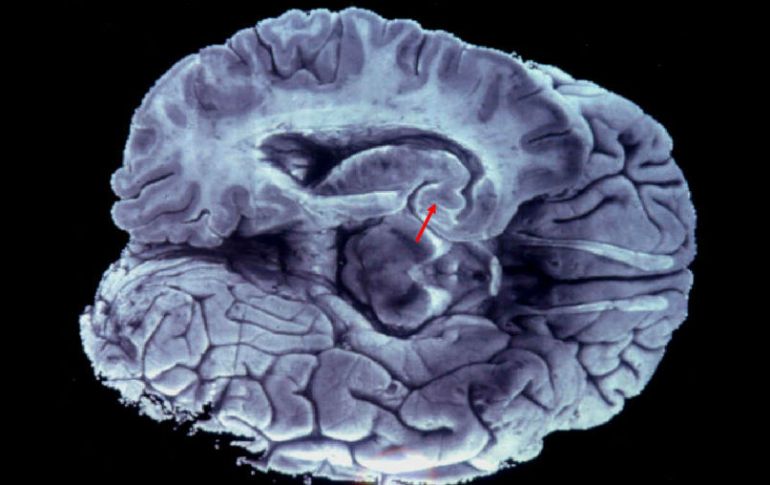

Tecnología | Un equipo de investigadores estadounidenses estudia las funciones del medicamento Un antiinflamatorio podría tratar los síntomas de demencia y alzheimer Un equipo de investigadores estadounidenses estudia el medicamento que revierte la disfunción relacionada con ambas enfermedades Por: EFE 21 de septiembre de 2015 - 10:59 hs Investigan desde hace tiempo el papel de la proteína tau en la demencia, pero se desconoce la toxicidad que lleva a la enfermedad. EFE / Archivo LONDRES, INGLATERRA (21/SEP/2015).- El salsalato, un medicamento antiinflamatorio indicado para el tratamiento del dolor leve o moderado, en especial la artritis reumatoide, podría servir para tratar los síntomas de la demencia o el alzheimer, aseguran. Un equipo del centro estadounidense Gladstones Institutes, encabezado por Li Gan, descubrió que el medicamento ''revierte la disfunción relacionada con la proteína tau (que se asocia a esas dos enfermedades) en un modelo animal de demencia frontotemporal''. En su experimento con ratones, los científicos hallaron que el salsalato ''previno la acumulación de tau en el cerebro y protegió contra unas discapacidades cognitivas parecidas a las que se aprecian en el caso del mal de Alzheimer y la demencia frontotemporal''. Según explican en la revista, el salsalato inhibe la acetilación de la proteína tau, un proceso que la convierte en más tóxica y que induce los procesos neurodegenerativos y los déficits cognitivos. La administración del fármaco rebajó los niveles de tau en el cerebro de los ratones, ''rescatando los daños a la memoria y protegiendo contra la atrofia del hipocampo''. ''Por primera vez, hemos identificado un enfoque farmacológico que revierte todos los aspectos de la toxicidad de tau'', asegura Gan. ''Los efectos protectores del salsalato se produjeron a pesar de que se administró cuando la enfermedad ya había aparecido, lo cual indica que podría ser una opción eficaz de tratamiento'', dijo. Aunque la comunidad científica investiga desde hace tiempo el papel de la proteína tau en la demencia, todavía se sabe poco del proceso por el que se acumula en el cerebro, causando la toxicidad que lleva a la enfermedad. ''Tratar la acetilación de tau podría ser una nueva estrategia terapéutica contra las patologías tau de los humanos, como el mal de Alzheimer y la demencia frontotemporal'', señala Eric Verdin, otro de los autores del estudio. Temas Ciencia médica Enfermedades Alzheimer Calor de hogar Lee También Estas son las vacunas recomendadas en época de frío Así ha bajado la afiliación de trabajadoras del hogar en el IMSS ¿Qué favorece la aparición de infecciones respiratorias? Estudio chino revela una mutación que eleva riesgo de alzhéimer Recibe las últimas noticias en tu e-mail Todo lo que necesitas saber para comenzar tu día Registrarse implica aceptar los Términos y Condiciones